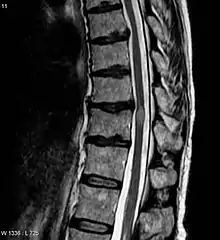

MRI image of transverse myelitis patient's spinal cord

Myelitis lesions usually occur in a narrow region but can be spread and affect many areas.